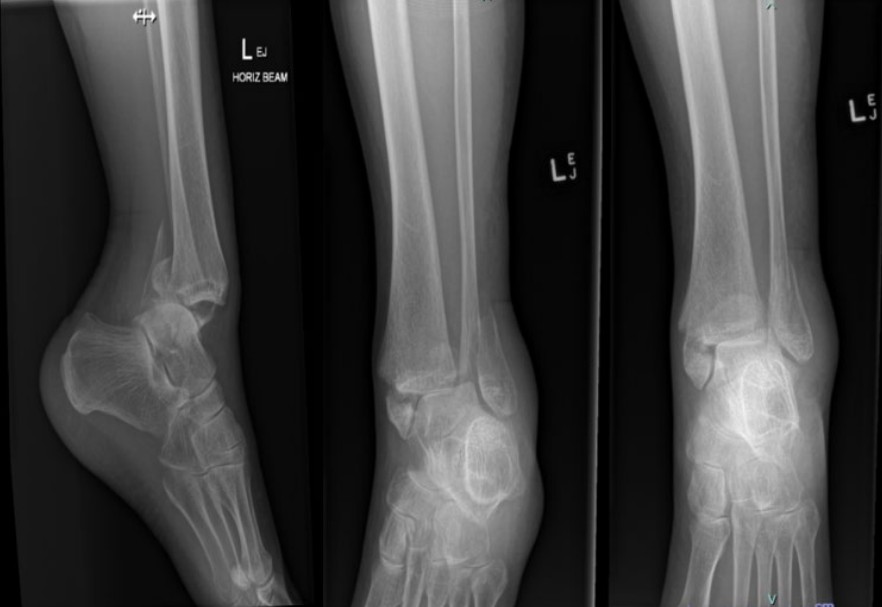

Trimalleolar ankle fracture-dislocation

A 65-year-old woman presents after slipping on a wet floor and is unable to weight-bear on her left ankle. X-rays …